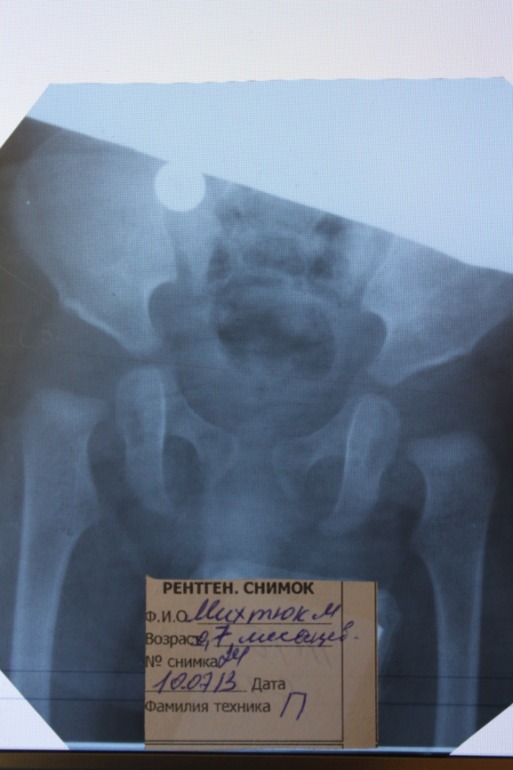

Добрый день! Поставили нам неутешительный диагноз. Хотя , вроде бы, все не так страшно. Расстраивает то, что достаточно поздно подтвердили диагноз. Однако разные врачи советуют разное лечение. Главный ортопед города сказал, что желательно гипсовать, так как ребенку уже 7 месяцев, по его мнению он выберется из шин. А второй уважаемый ортопед нашего города сказал, что вывиха нет и гипс ни к чему, достаточно обойтись отводящей шиной, гимнастикой, массажем и кальцеванием с парафином. Однако какой именно не сказал, нашли шину Виленского, но пока не могу проконсультироваться с врачом.. Думаю, что подушку Фрейка нам уже будет не удобно носить, а Орлет у нас не достать, только под заказ и ждать две недели.. В общем, не знаем какое лечение выбрать. Может быть , кто-нибудь сможет поделиться своим опытом? Есть еще более свежие результаты узи, там узи суставов делалось под нагрузкой